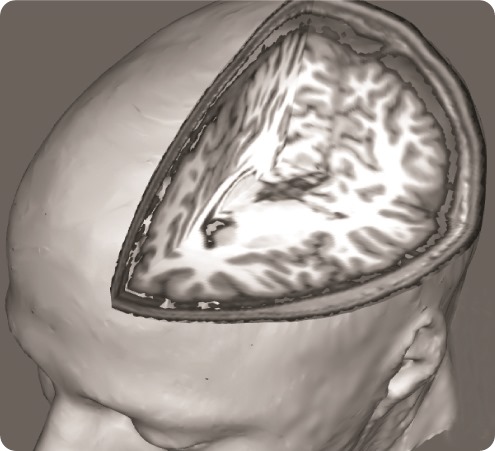

In order to address this question, we used a brain imaging technique called ‘functional Magnetic Resonance Imaging’, which allows us to examine how brain activity changes in association with certain states or tasks.

In this study brain activity was investigated when the participants received painful stimuli, as well as when they received visual cues informing the subjects of impending pain onset (pain anticipation) and pain offset (relief anticipation).

In terms of pain stimulation, we use a vascular cuff, similar to the one used to measure blood pressure, placed on the leg. Of note, this type of stimulation is different from what is typically used in brain imaging studies (e.g., contact heat probes placed on the skin), because the ‘pain receptors’ it targets are located more in the deep tissue, rather than on the skin, and thus we think it may generate a pain sensation that is closer to the clinical pain of fibromyalgia.